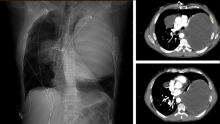

The patient is a forty-five-year-old man with metastatic testicular cancer, who underwent four cycles of chemotherapy with a complete response. Surveillance imaging revealed a 21 x 15 x 12-centimeter mass in the left chest and an 8-centimeter mass in the right upper lobe, consistent with metastasis.